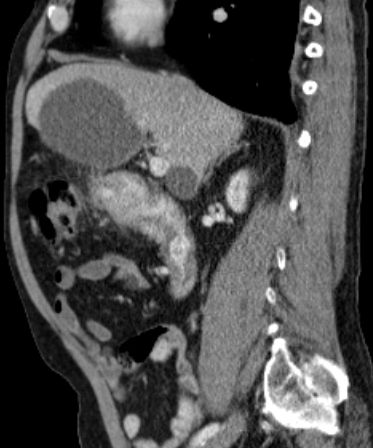

aortaler Bulk |

80-jähriger Mann mit einem retroperitonealen NHL.![]() |